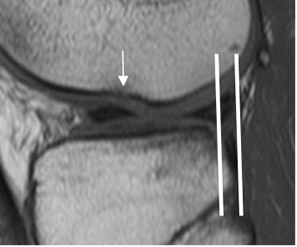

Fig 105. Angulación del LCP.

A: RM sagital en T2. Angulo normal en promedio de 123º.

B: RM sagital en T2. Disminución del ángulo, menor de 107º, como signo secundario de ruptura del LCA.